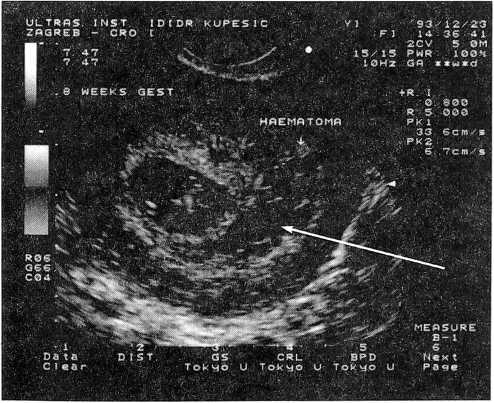

Рис. 1. Беременность 8 недель; визуализируется ретрохориальная гематома (показано стрелкой)

В случае самопроизвольного аборта внутриматочные гематомы визуализируются в виде эхонегативного полукруга или клинообразной структуры между тканью хориона и стенкой матки [37]. По локализации их разделяют на ретроплацентарные, субхорионические, краевые или супрацервикальные [37, 39, 40]. Наиболее неблагоприятными являются большие центральные ретроплацентарные гематомы, которые приводят к отслойки части хориона от децидуальной оболочки.

Поскольку одной из причин самопроизвольного аборта являются сосудистые нарушения, оценка кровообращения в плаценте на ранних сроках беременности может быть полезной для прогнозирования ее исхода. Однако в настоящее время сведения о характере маточно-плацентарного и плодового кровотока после формирования внутриматочных гематом являются неоднозначными. Так, по данным Kurjak А. и сотр., на стороне субхориальной гематомы наблюдалась повышенная резистентность кровотоку и снижение его скорости в бассейне спиральных артерий, что авторы объясняли механическим давлением гематомы [37, 38]. При этом Alcazar J. L. и сотр. не выявили изменений кровообращения при ретрохориальной локализации гематомы на ранних этапах беременности. Большинство гематом в этом исследовании были небольшими по размеру, имели краевое расположение и могли не оказывать существенного влияния на характер плодового кровообращения [42]. Даже в случае центрально расположенной гематомы авторы не обнаружили никаких изменений в гемодинамике плода при сопоставлении с контрольной группой. Подобные результаты были получены также Kurjak А. и сотр.[43], Rizzo G. и сотр. [44], Stabile I. и др. [47]. Предполагается, что при угрожающем выкидыше в I триместре беременности сосудистые нарушения минимальны и могут быть не обнаружены с помощью допплеровского метода исследования [48].